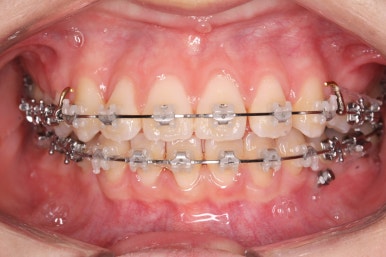

부산교정 키다리아저씨치과에서 장치를 부착하고 교정치료를 시작하였습니다.

이번에 부착한 장치는 엠파워클리어라고 하는 자가결찰 세라믹 장치입니다. 흔히들 클리피씨 장치로 많이 알고 계신 장치가 바로 자가결찰 세라믹 장치인데요.

자가결찰 세라믹 장치 중 또 다른 하나가 엠파워 클리어입니다. 클리피씨는 일본제품, 엠파워 클리어는 미국제품으로 제조회사가 다를 뿐 큰 분류에서는 비슷한 장치라고 보시면 되겠습니다.

가지런하게 하는 작업을 계속 합니다.

또한 왼쪽 위 작은 어금니 하나를 추가로 발치했습니다. 치아 갯수를 맞출 목적 + 우측으로 쏠린 앞니의 중앙을 개선하기 위함 입니다.

이제 어느 정도 치열이 가지런해졌습니다. 앞으로 해야 될 단계는 앞니 틈을 줄이고, 이 뽑은 자리 틈을 줄이면서 중앙선을 개선하고 아래쪽 어금니를 앞으로 당겨오면서 교합을 맞추며 앞니 갯수를 맞춰줍니다.